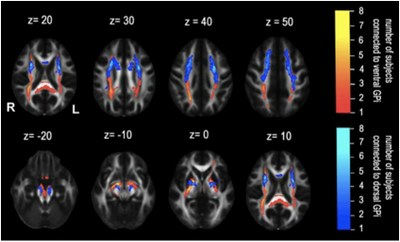

“We have worked with multimodal MRI (Magnetic Resonance Imaging) from patients with dystonia treated with deep brain stimulation (DBS), and we have found where the neural fibres originating closest to the stimulation electrodes projected”, explains the researcher João Paulo Cunha. The researchers have found a significant difference in the antero-posterior distribution of the fibres close to the sensory motor cortical lateral areas between the ventral and dorsal GPI. The realisation that there are different connection profiles between the GPI and the cortex confirms that the ventral and dorsal GPI belong to different functional and anatomic motor subsystems. Also according to the paper, the consideration of the previously described factors can also play an important role when promoting the DBS clinical effects in patients suffering from dystonia.